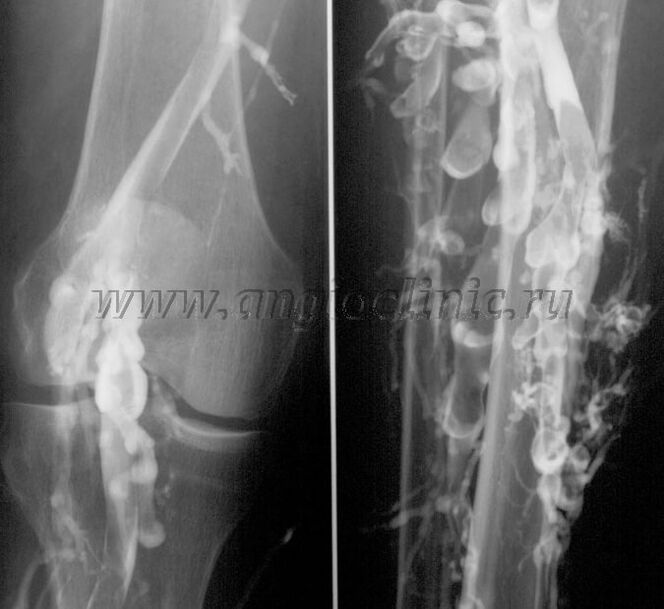

Venografia contrastada

Normalmente, a ultrassonografia é suficiente para um diagnóstico completo da patologia venosa, mas em alguns casos é necessário estudar a relação entre o estado do sistema venoso profundo e superficial, principalmente no caso de recidivas de varizes e varizes secundárias.

Para resolver esses problemas, é utilizado o exame de raios X contrastados. As veias safenas são puncionadas e o contraste é administrado. O movimento do contraste é observado no monitor do aparelho de raios X, e todos os testes e projeções necessários são realizados. Atualmente, a venografia para varizes é usada muito raramente.